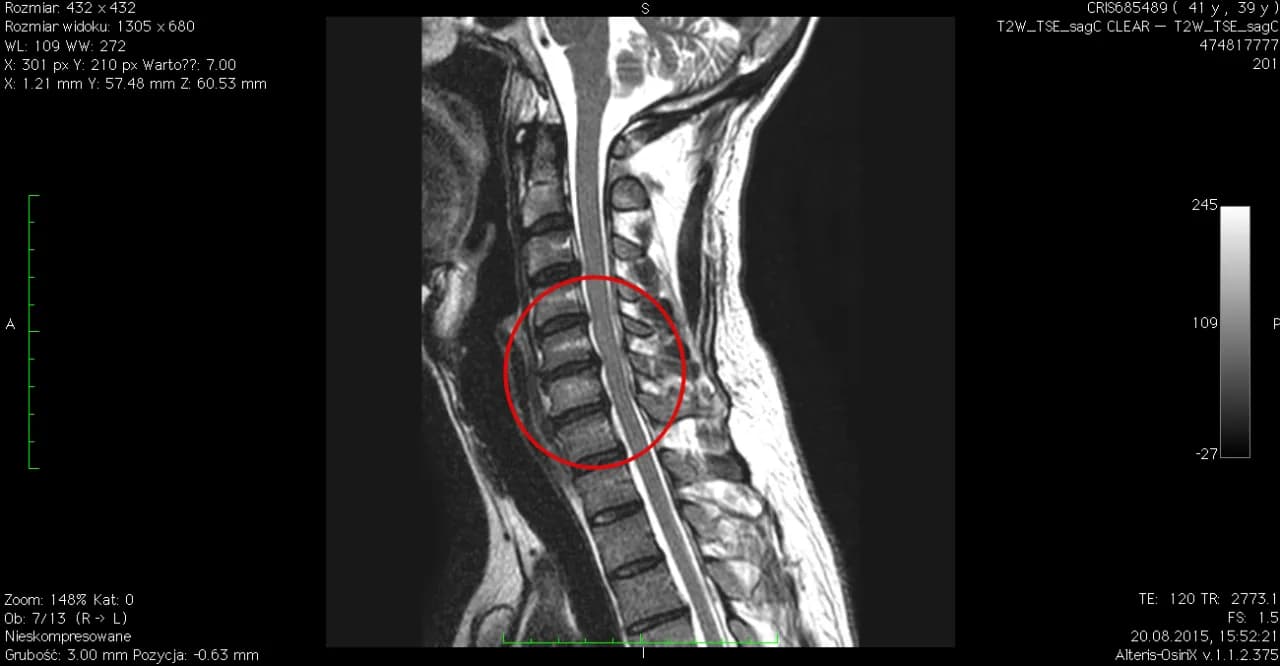

Badania obrazowe są kluczowe dla potwierdzenia diagnozy. Rezonans magnetyczny (MRI) pozwala dokładnie uwidocznić struktury miękkie, w tym krążki międzykręgowe i nerwy. Tomografia komputerowa (CT) może być pomocna w ocenie zmian kostnych. Oba badania umożliwiają określenie stopnia uszkodzenia krążka i ucisku na struktury nerwowe.